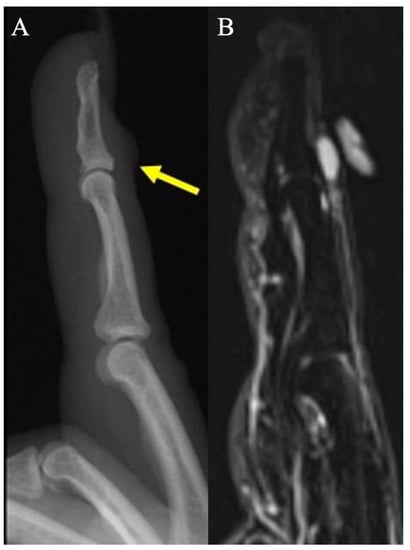

2.10. Foreign Bodies of the Hand

2.10.1. Clinical Features

2.10.2. Imaging Appearance